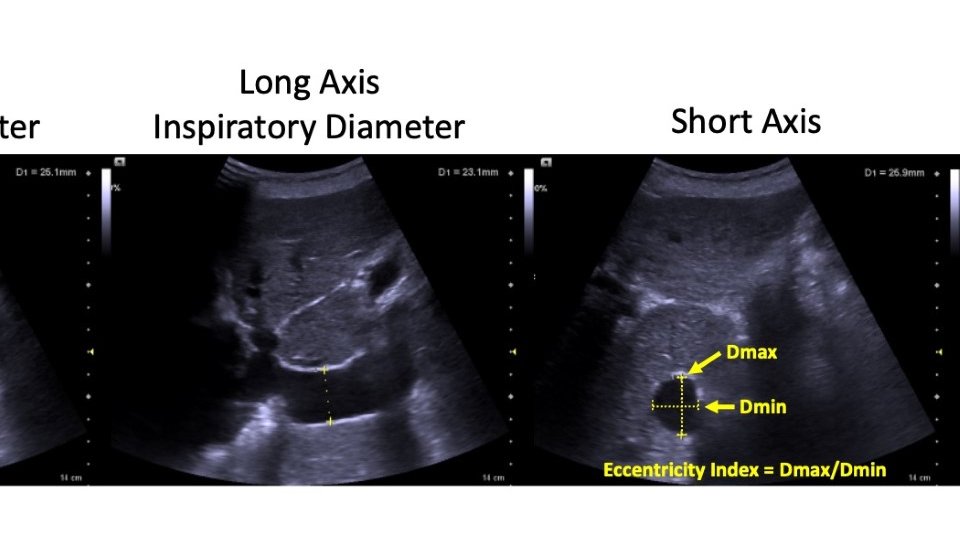

Instead, I try to think of where on the spectrum from fully collapsed IVC to fully plethoric it lies (considering short axis and long axis for as much of the intrahepatic IVC as possible).

You can have severe venous congestion with an IVC of 1.5 cm and no venous congestion with an IVC of 4cm.

But remember, similar to other veins, the IVC is not round. Interrogating the IVC only in long axis ignores this fact. I try to interrogate the entire intrahepatic IVC in long and short axis to get a general gestalt of degree of distension.